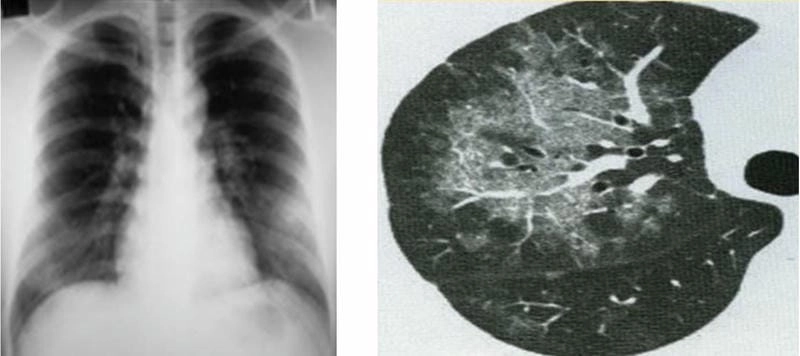

Bạn sẽ phải rùng mình khi chiêm ngưỡng hình ảnh bệnh lao phổi là như thế nào dưới ống kính y học thực tế. Những bức ảnh chụp X-quang cho thấy phổi bị tổn thương nặng, xuất hiện những đốm trắng mờ như bóng ma ám ảnh. Không chỉ là các tổn thương vật lý, đây còn là những “chứng tích sống” của căn bệnh âm thầm hủy hoại cơ thể qua từng hơi thở. Từ viêm nhẹ đến tổn thương lan rộng, hình ảnh bệnh lao phổi khiến người xem không thể rời mắt vì mức độ nghiêm trọng mà nó thể hiện rõ ràng qua từng chi tiết.

Cảnh báo: tổng hợp ảnh bệnh lao phổi chân thực này không dành cho người yếu tim. Đây là loạt hình ảnh y khoa được các chuyên gia sưu tầm và xác thực, ghi lại quá trình tiến triển của bệnh từ giai đoạn đầu đến giai đoạn nguy kịch. Từng mảng mô phổi bị ăn mòn, xơ hóa, hoại tử được phơi bày rõ nét dưới ánh sáng X-quang lạnh lùng. Những hình ảnh này không chỉ mang tính chất minh họa y học, mà còn là hồi chuông cảnh tỉnh cho bất kỳ ai còn lơ là với căn bệnh nguy hiểm này.